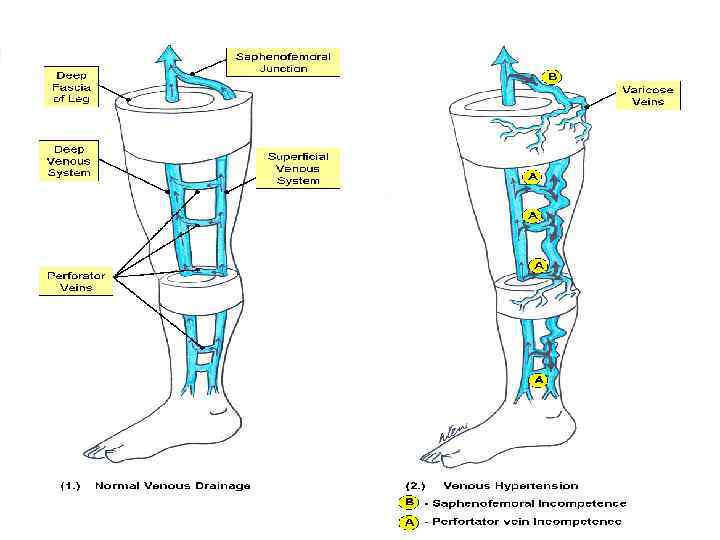

Причины ТЭЛА Хроническая венозная недостаточность – болезнь каждой 4 -ой женщины